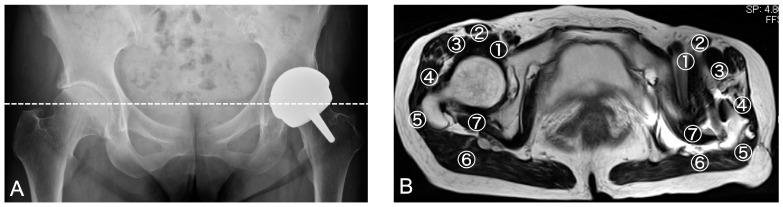

We enrolled 45 hips from 40 HRA patients with a mean follow-up period of 8.2 years. MRI and ultrasonography scans were simultaneously conducted at follow-up. The ultrasonography assessments were conducted on the anterior part of the hip that targets iliopsoas, sartorius, rectus femoris, lateral with anterior superior and inferior iliac spine (ASIS and AIIS) as bony landmarks, and the lateral and posterior parts that target fascia tensor, short rotators, and gluteus minimus, medius, and maximus with greater trochanter and ischial tuberosity as bony landmarks. The accuracy of diagnosing postoperative abnormalities and the visibility of periprosthetic muscles were compared between these two modalities.

Both MRI and ultrasonography detected an abnormal region in eight cases comprising two infections, two pseudotumors, and four patients with greater trochanteric bursitis. Among these cases, four hips required implant removal. The increase in anterior space, measured as the distance between the iliopsoas and resurfacing head, was a good indicator for the abnormal mass in these four HRA cases. In the assessment of periprosthetic muscles, MRI showed a much lower visibility than ultrasonography in the iliopsoas (6.7% vs. 100%), gluteus minimus (6.7% vs. 88.9%), and short rotators (8.8% vs. 71.4%) due to implant halation.